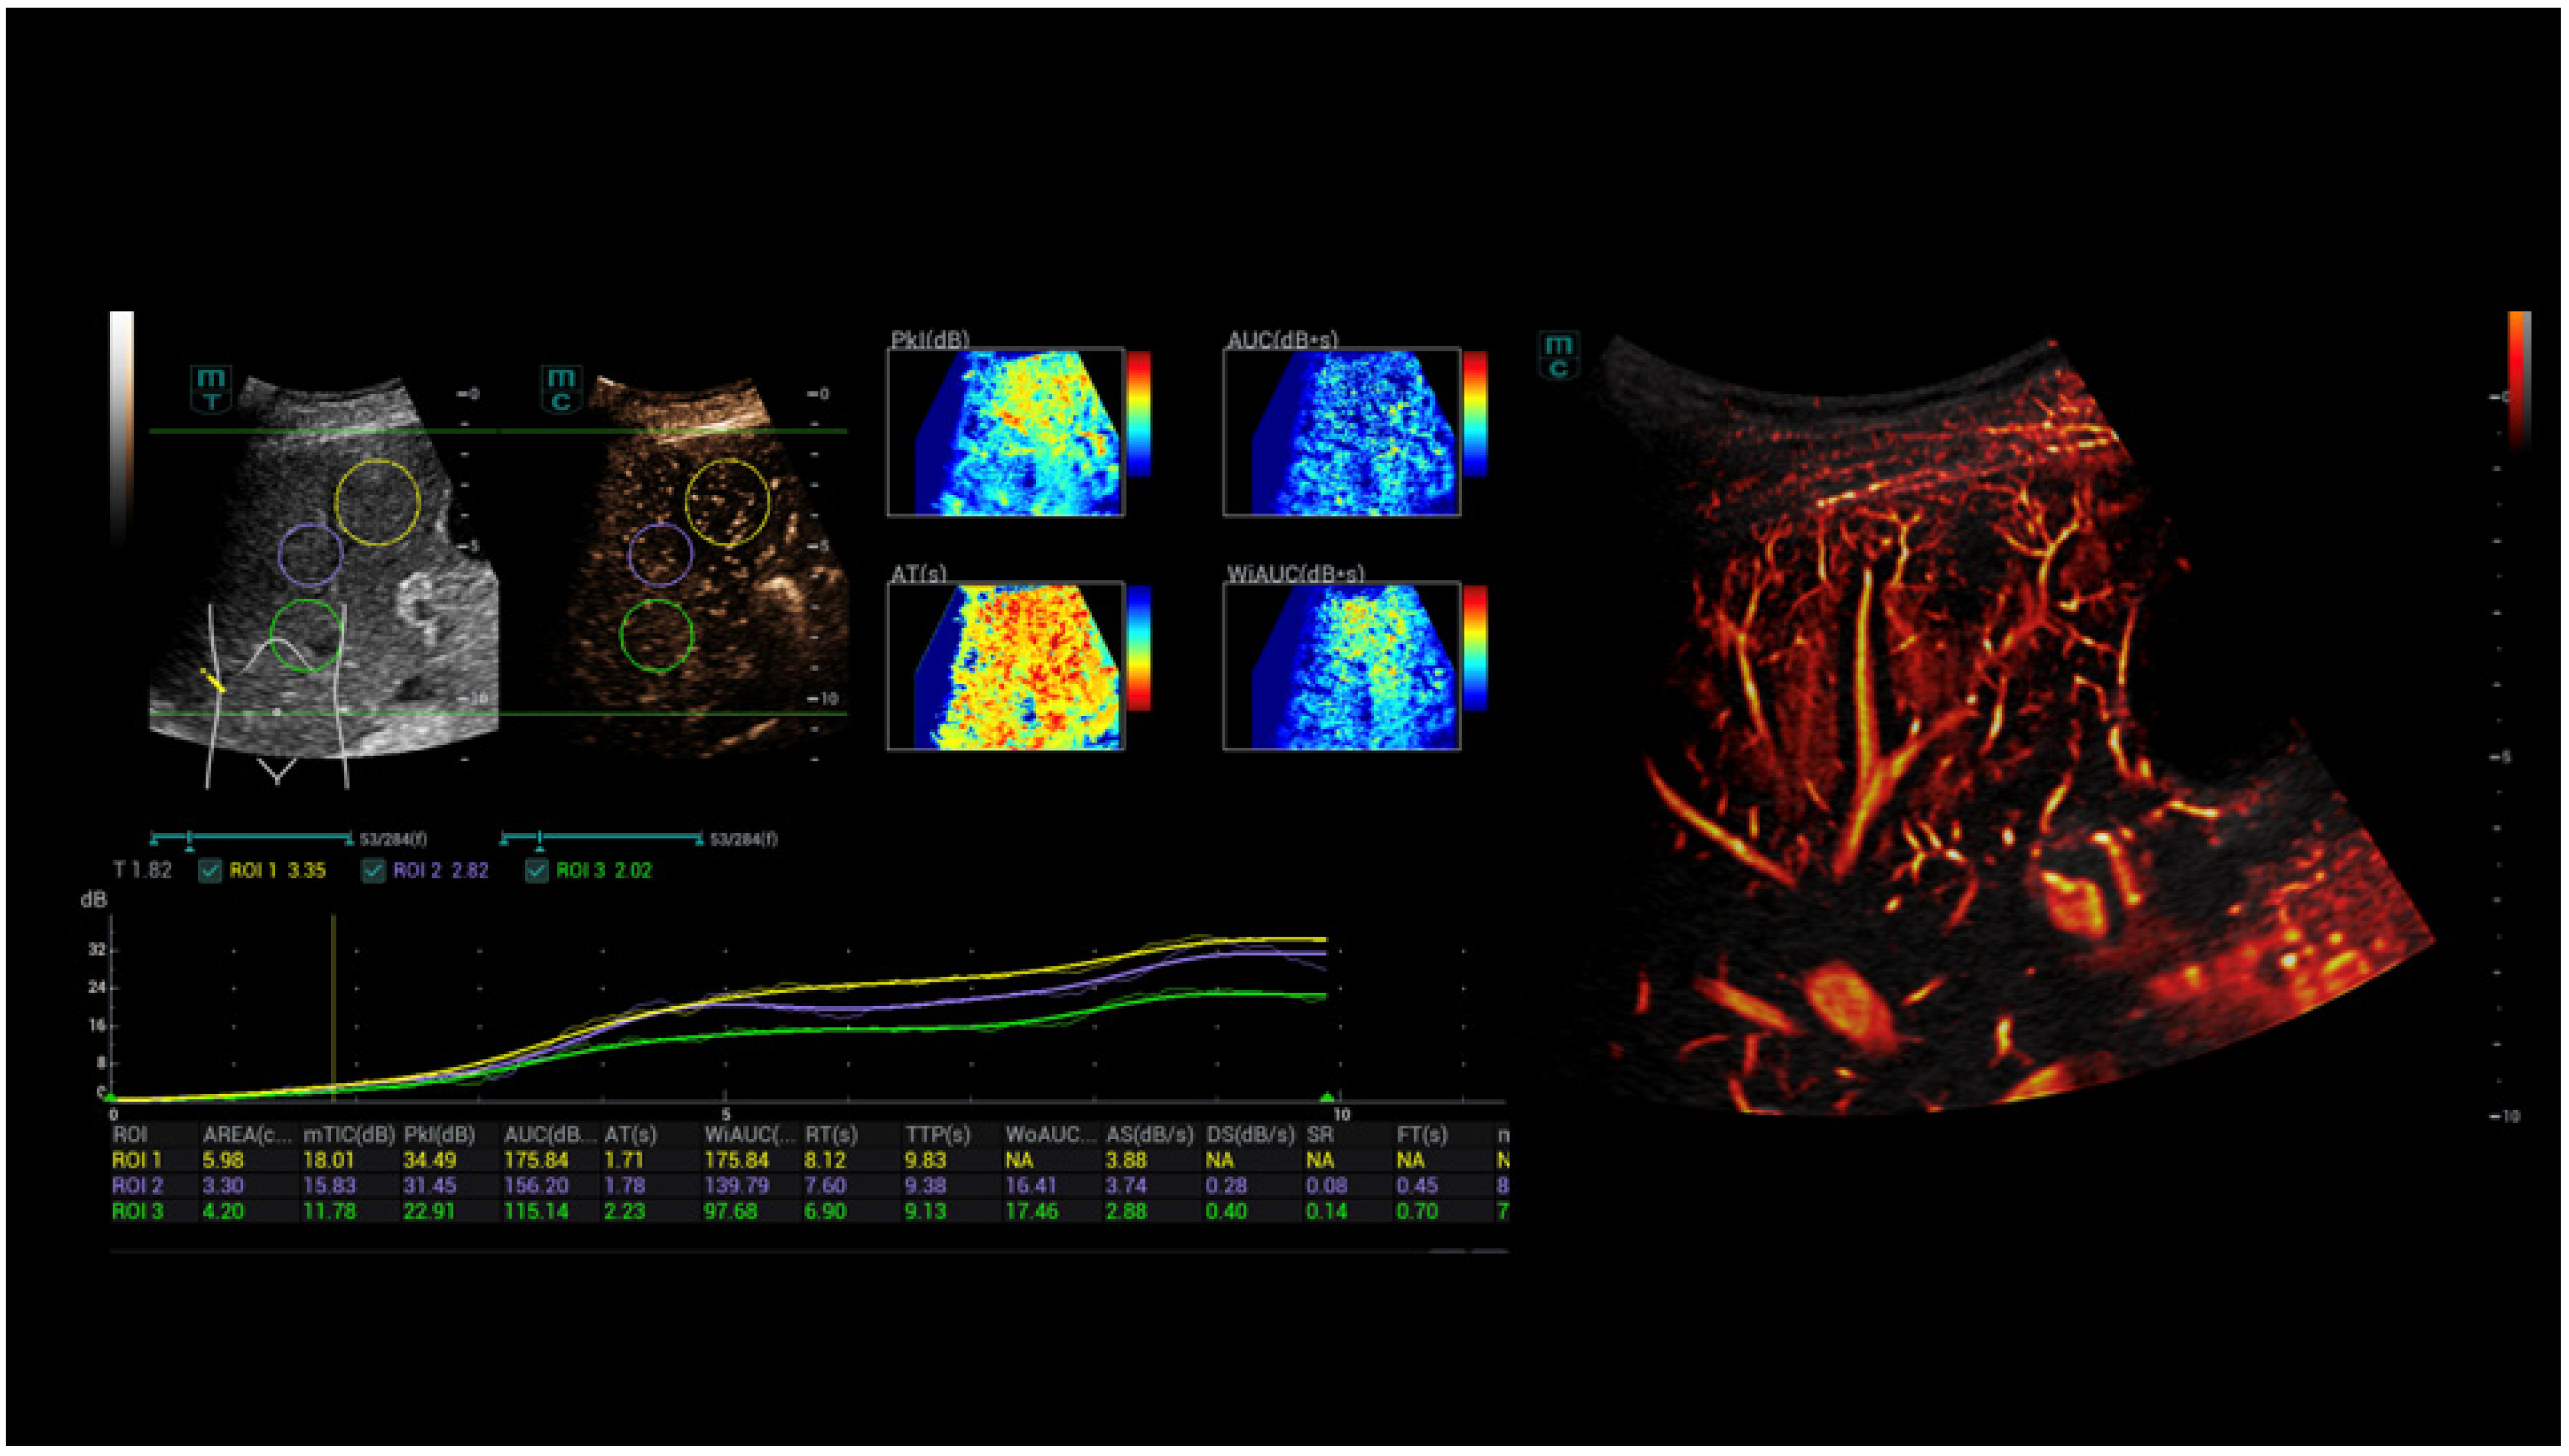

- Schelker, R.C.; Andorfer, K.; Putz, F.; Herr, W.; Jung, E.M. Identification of two distinct hereditary hemorrhagic telangiectasia patient subsets with different hepatic perfusion properties by combination of contrast-enhanced ultrasound (CEUS) with perfusion imaging quantification. PLoS ONE 2019, 14, e0215178. [Google Scholar] [CrossRef]